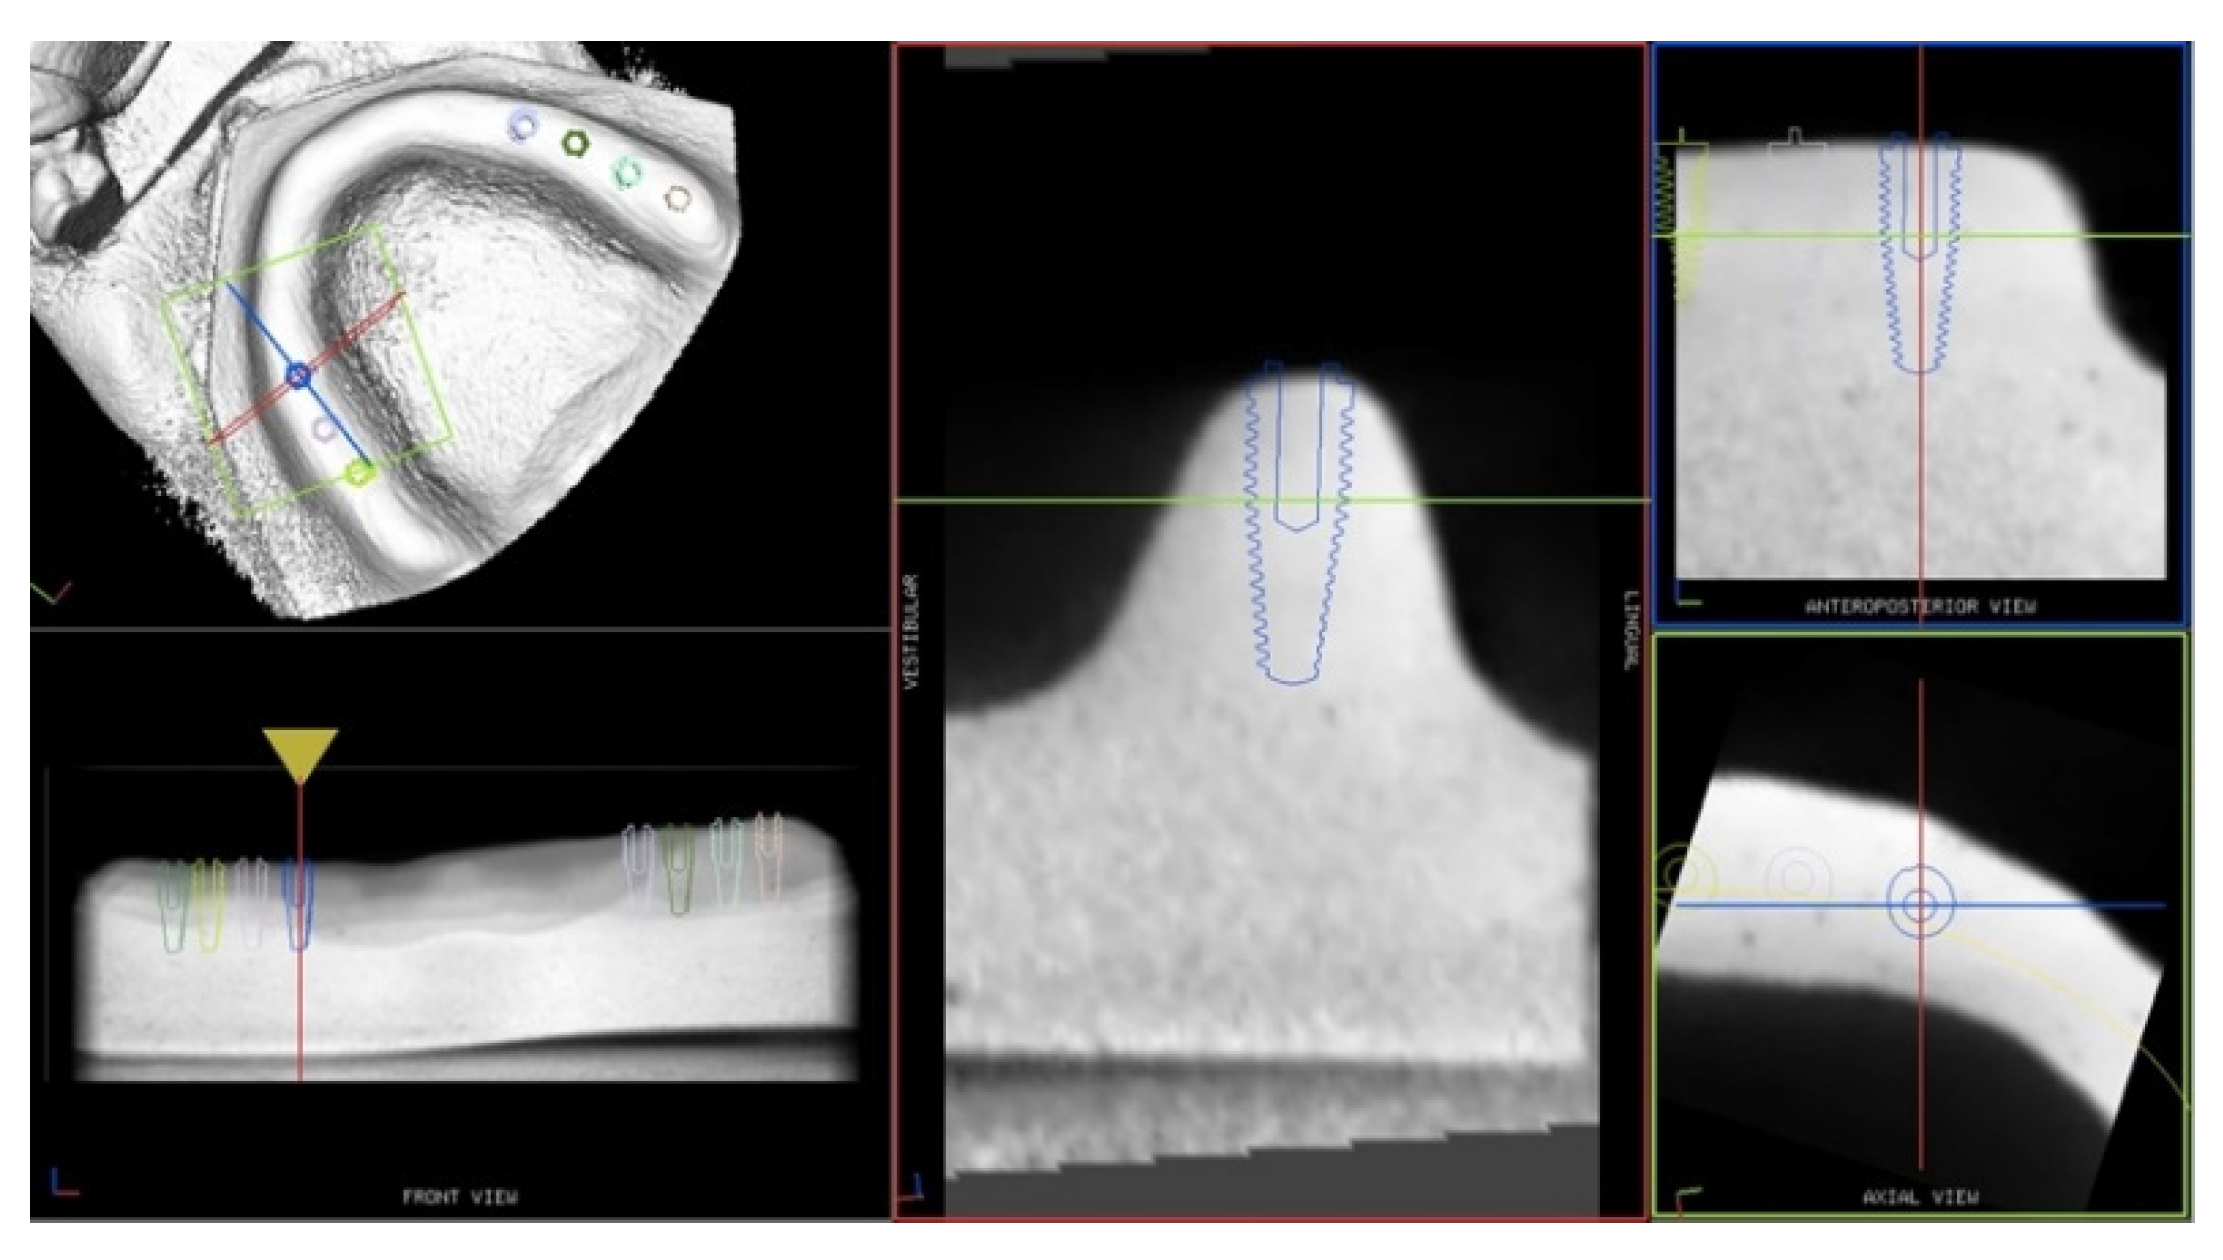

The drilling procedure was performed with conical shaped drills (Southern Implants, Irene, South Africa) calibrated on a 4 × 11.5 mm implant using a dynamic navigation system (ImplaNav, BresMedical, Sydney, Australia). Thanks to the navigation system, the operator was able to follow the drill position in real-time on the system screen displaying the CBCT images of the model and the implant plan (Figure 3).

Figure 3.

Screen display of the navigation system during implant site preparation.